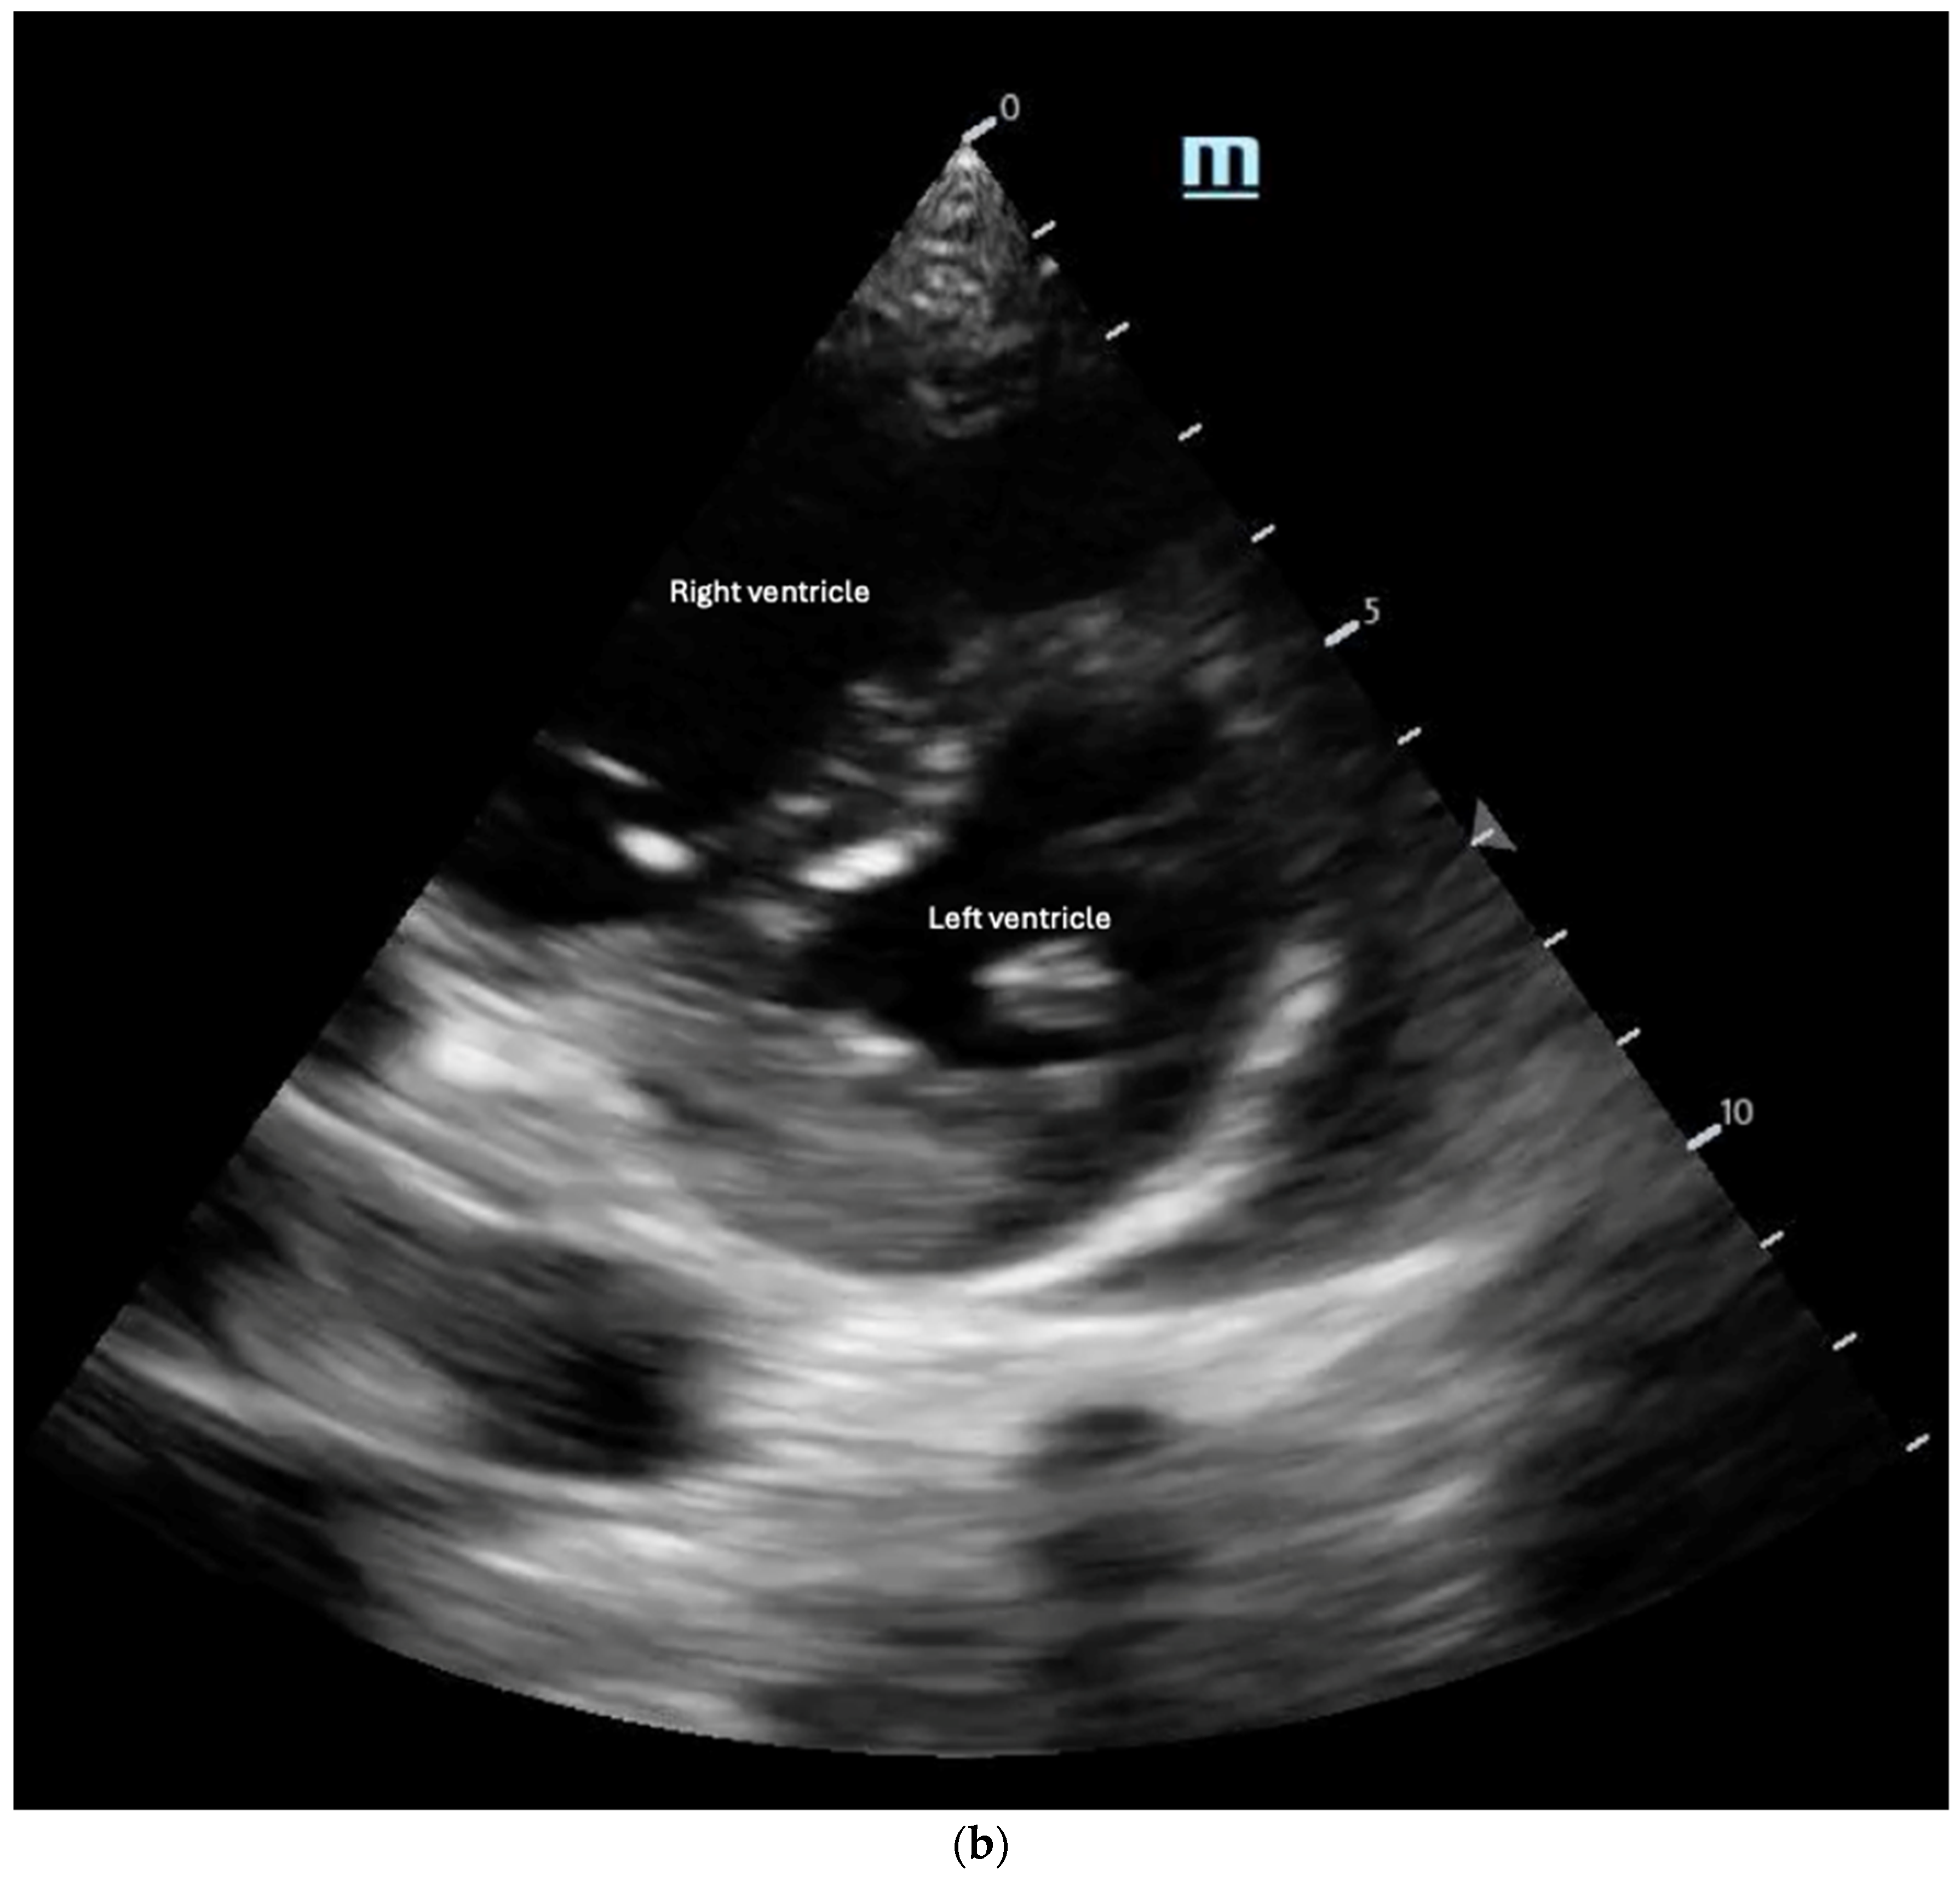

Figure 8. (a) Tricuspid regurgitation velocity (TRV) measured by continuous wave (CW) Doppler in apical 4-chamber view. (b) D sign in parasternal short axis view in diastolic frame. Note flattening of the interventricular septum. - McConnell’s sign: A POCUS finding defined as hypo or akinesis of the mid-RV free wall with preserved apical contraction on ultrasound is a widely recognized marker of right heart strain, particularly in the setting of acute pulmonary embolism (PE) [32,35]. In the original 1996 study describing McConnell’s sign, a sensitivity of 77% and a specificity of 94% were markers for acute PE, even after comparison with patients with other causes of RV dysfunction, such as pulmonary hypertension [45,46]. However, additional studies since then have cast doubt on the high specificity of McConnell’s sign, with one study showing equal prevalence of McConnell’s sign in patients with acute PE or RV myocardial infarction and another study demonstrating that patients diagnosed with acute PE with McConnell’s sign present had similar echocardiographic findings as a comparison group of patients with chronic pulmonary hypertension [47,48]. In contrast, a recent meta-analysis still found a pooled sensitivity of 22% and specificity of 97% for McConnell’s sign in the setting of acute PE, although they noted that high suspicion for acute PE prompted POCUS use in the majority of the studies [49]. Its positive predictive value ranges between 57 and 71% [50]. These findings suggest that while McConnell’s sign may be consistent with right heart strain in acute PE, caution should be utilized regarding its diagnostic capabilities for PE. Accordingly, in 2010, the American Society of Echocardiography and American College of Emergency Physicians recommended against the sole use of POCUS and McConnell’s sign for diagnosing and treating presumed acute PE except in patients too unstable to undergo additional confirmatory testing such as CT imaging [51].

- The “D-Sign”: This refers to the flattening of the interventricular septum with a leftward deviation into the left ventricle, causing the left ventricle to appear as a D-shaped structure, as seen in the parasternal short-axis view (Figure 8b). This finding suggests increased RV afterload and can be associated with pulmonary hypertension, acute PE, and RV failure [35]. Diastolic septal flattening indicates volume overload (e.g., severe tricuspid regurgitation or atrial septal defect), while systolic flattening points to pressure overload (e.g., pulmonary hypertension or acute PE). In volume overload, the D shape is most pronounced at end-diastole and resolves in systole, whereas in pressure overload, flattening persists throughout the cardiac cycle [36].